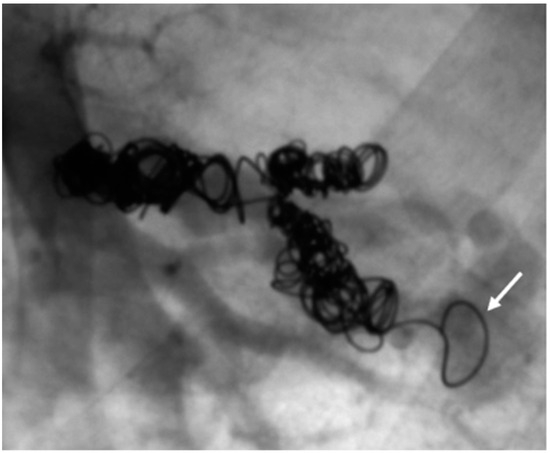

In another patient, however, the formation of collaterals between the intercostal and pulmonary arteries in the sense of aortopulmonary collaterals was detected (Figure 13 and Figure 14). Figure 15 also schematically shows the reperfusion mechanism of embolized PAVM with collateral formation.

Figure 13. MRA (left) with presentation of collateral vessels by the systemic circulation supplying the PAVM (open arrow) and confirmation by DSA (right).

Figure 14. DSA with presentation of embolized collaterals between intercostal and pulmonary arteries.